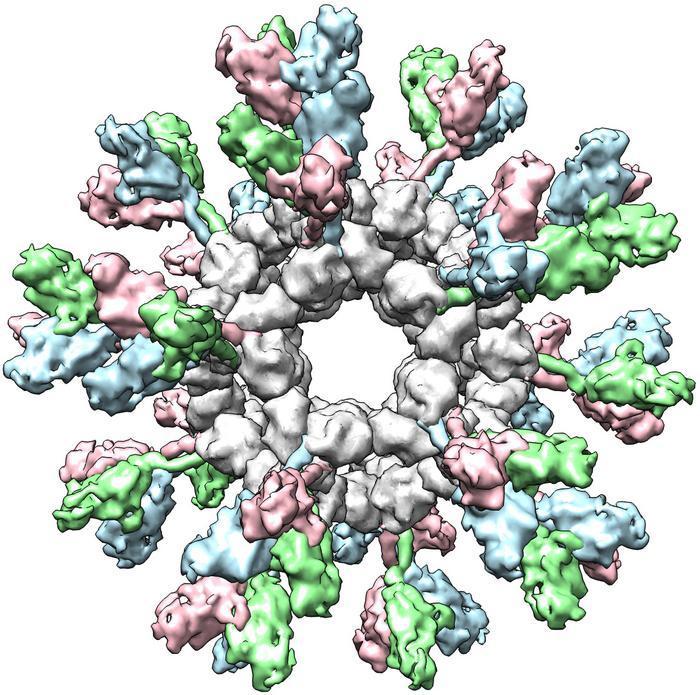

將納米顆粒轉化為病毒“展示盒”,全新疫苗策略可預防致命絲狀病毒感染

科技日報

2025-12-22 01:45:00